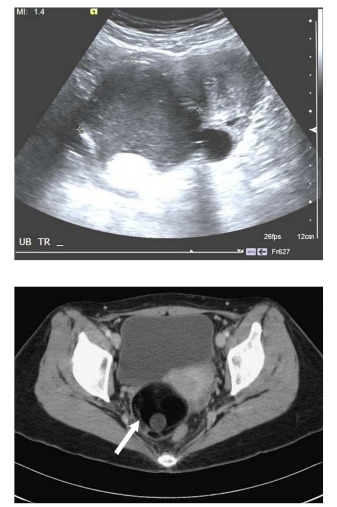

75. 43歲女性病人,健檢時發現CA-199升高,接受腹部影像檢查,上圖為骨盆處橫切超音波,下圖為CT最可能之診斷為何?

(A)卵巢癌(ovarian cancer)

(B)卵巢畸胎瘤(ovarian teratoma)

(C)子宮內膜異位(endometriosis)

(D)卵巢濾泡囊腫(ovarian follicular cyst)